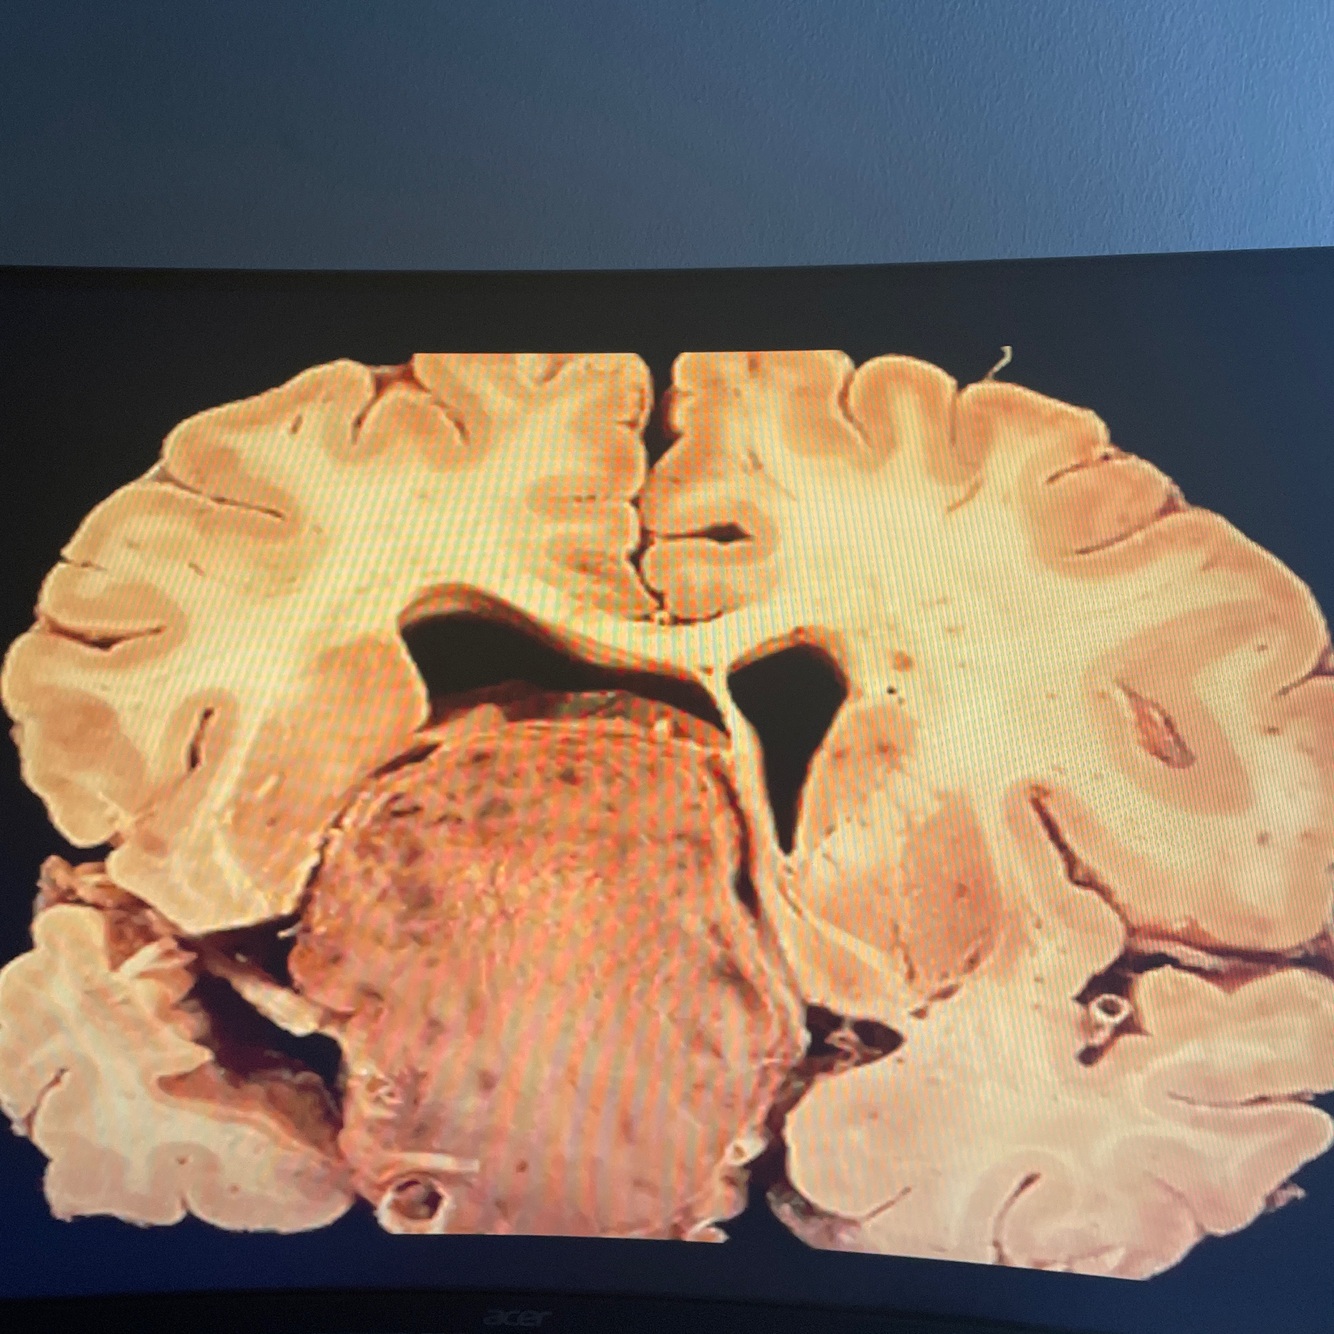

Craniopharingioma most common cause ofhypituatarism in children